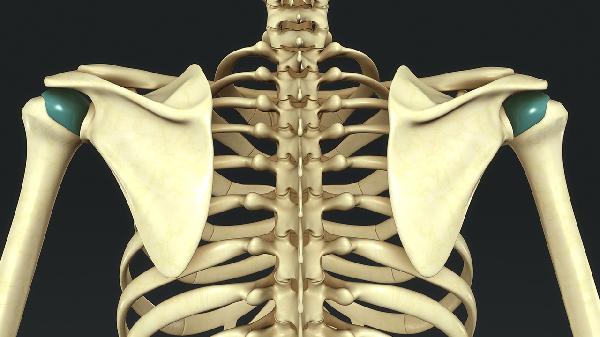

胸椎压迫神经表现

胸椎压迫神经主要表现为胸背部疼痛、肢体麻木、肌力下降、感觉异常及内脏功能障碍。胸椎压迫神经可能与椎间盘突出、胸椎管狭窄、胸椎骨折、胸椎肿瘤、胸椎结核等因素有关,通常表现为胸背部放射性疼痛、下肢无力、排尿困难等症状。建议及时就医,完善影像学评估,根据病因选择物理治疗、药物干预或手术减压。